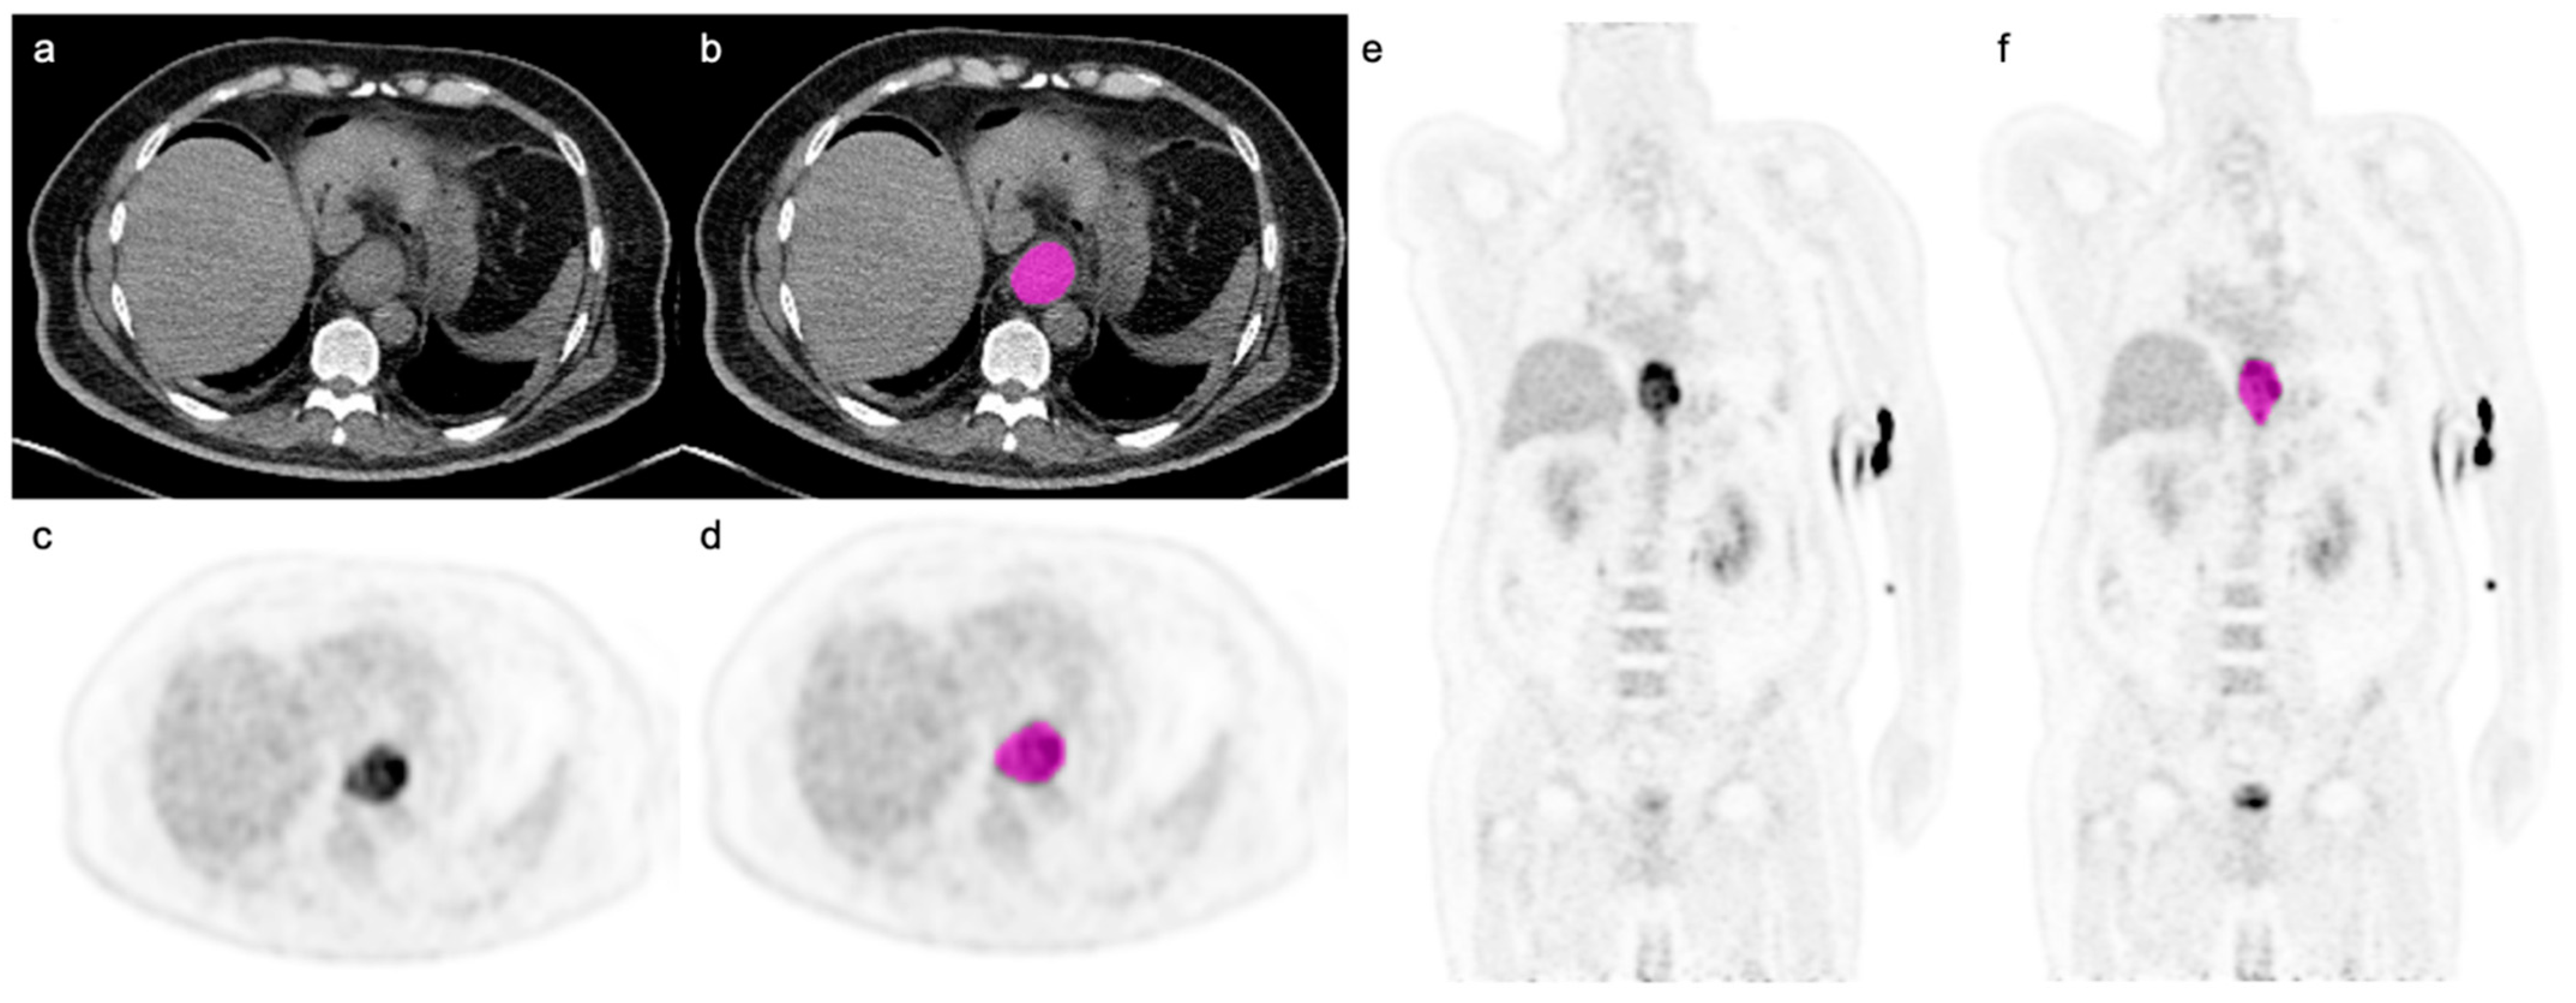

2.2. Image Analysis and Sarcopenia Measurements

2.3. Image Segmentation and Radiomic Feature Extraction